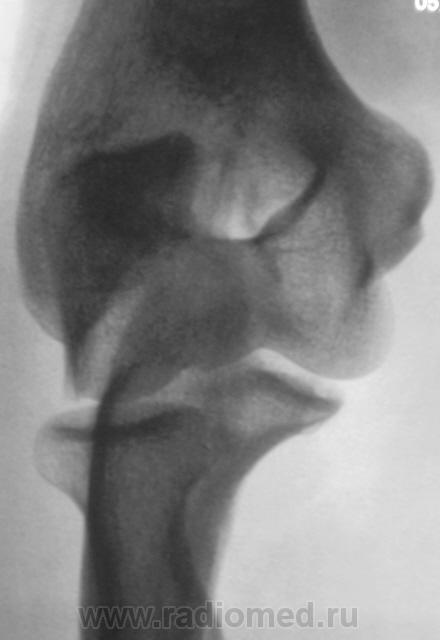

Травма. Пациент направлен на рентгенографию локтевого сустава.

Перелом локтевого отростка - на операцию

Если рассуждать с точки зрения только диагностики перелома - нет, так как перелом хорошо виден и на стандартных проекциях. С точки зрения дальнейшей лечебной тактики - да. Так как косые проекции выявили безусловную необходимость оперативного лечения.